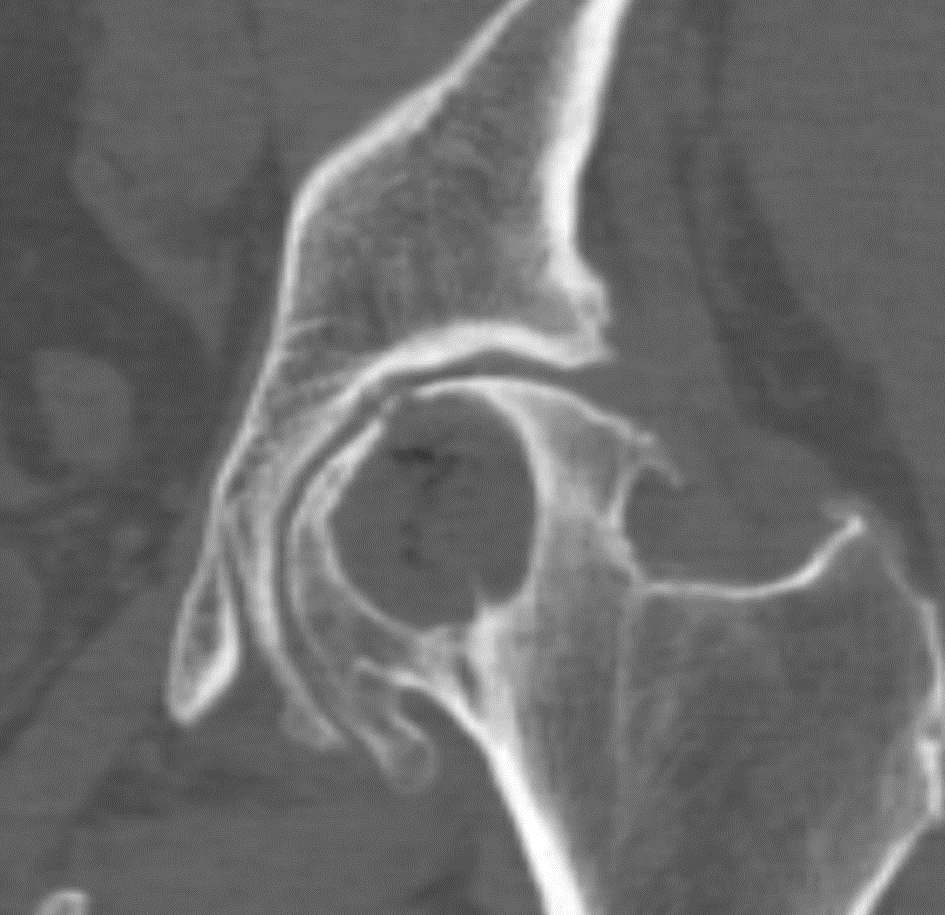

Диагностика

Все кистозные образования выявляются с помощью различных инструментальных методов исследования. Однако тазобедренный сустав находится в труднодоступном месте, что затрудняет рентгенологические процедуры. Киста расположена глубоко в мягких тканях, что усложняет диагностику. Поэтому для определения наличия кисты рекомендуется использовать:

- УЗИ (ультразвуковое исследование);

- КТ (компьютерная томография);

- МРТ (магнитно-резонансная томография);

- артроскопию.